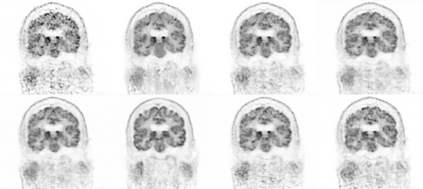

Due to various physical degradation factors and limited counts received, PET image quality needs further improvements. The denoising diffusion probabilistic models (DDPM) are distribution learning-based models, which try to transform a normal distribution into a specific data distribution based on iterative refinements. In this work, we proposed and evaluated different DDPM-based methods for PET image denoising. Under the DDPM framework, one way to perform PET image denoising is to provide the PET image and/or the prior image as the network input. Another way is to supply the prior image as the input with the PET image included in the refinement steps, which can fit for scenarios of different noise levels. 120 18F-FDG datasets and 140 18F-MK-6240 datasets were utilized to evaluate the proposed DDPM-based methods. Quantification show that the DDPM-based frameworks with PET information included can generate better results than the nonlocal mean and Unet-based denoising methods. Adding additional MR prior in the model can help achieve better performance and further reduce the uncertainty during image denoising. Solely relying on MR prior while ignoring the PET information can result in large bias. Regional and surface quantification shows that employing MR prior as the network input while embedding PET image as a data-consistency constraint during inference can achieve the best performance. In summary, DDPM-based PET image denoising is a flexible framework, which can efficiently utilize prior information and achieve better performance than the nonlocal mean and Unet-based denoising methods.